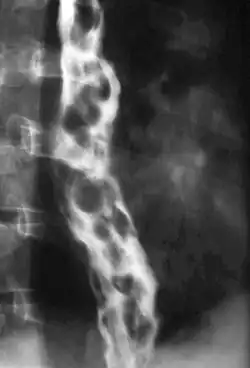

Esophageal varices are extremely dilated sub-mucosal veins in the lower third of the esophagus.[1] They are most often a consequence of portal hypertension,[2] commonly due to cirrhosis.[3] People with esophageal varices have a strong tendency to develop severe bleeding which left untreated can be fatal. Esophageal varices are typically diagnosed through an esophagogastroduodenoscopy.[4]

Dilated submucosal veins are the most prominent histologic feature of esophageal varices. The expansion of the submucosa leads to elevation of the mucosa above the surrounding tissue, which is apparent during endoscopy and is a key diagnostic feature. Evidence of recent variceal hemorrhage includes necrosis and ulceration of the mucosa. Evidence of past variceal hemorrhage includes inflammation and venous thrombosis.